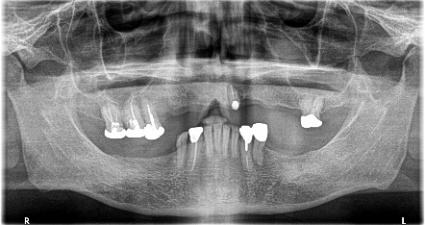

男性 Kさん 60代 (インプラント)

主訴

下の左右歯がないところに歯を入れたい。

治療内容

左右それぞれ3本歯がないところに2本ずつインプラントを埋入しました。

所感

上と下の歯の咬合接触がないすれ違い咬合です。上下義歯で対応するには最も難しいタイプの欠損状況です。治療開始前は、上下部分入れ歯が入っていましたが、入れ歯の安定が悪く、あちこちの歯茎に入れ歯が当たって痛く、満足に噛める状態ではありませんでした。上顎は、残ってる歯を活用するマグネット式総義歯を、下顎はインプラントを提案しました。上顎は、現在残っている歯の根管治療中です。上顎にマグネット式総義歯がはいれば、何でも食べられるようになります。

インプラント4本:¥363,000×4本=¥1,452,000(税込)

ポンティック2本:¥115,500×2本=¥231,000(税込)

合計:¥1,683,000(税込)

Before

▼初診時に使用していた部分入れ歯を装着したところ

▼インプラント埋入前

After

▼インプラント埋入後